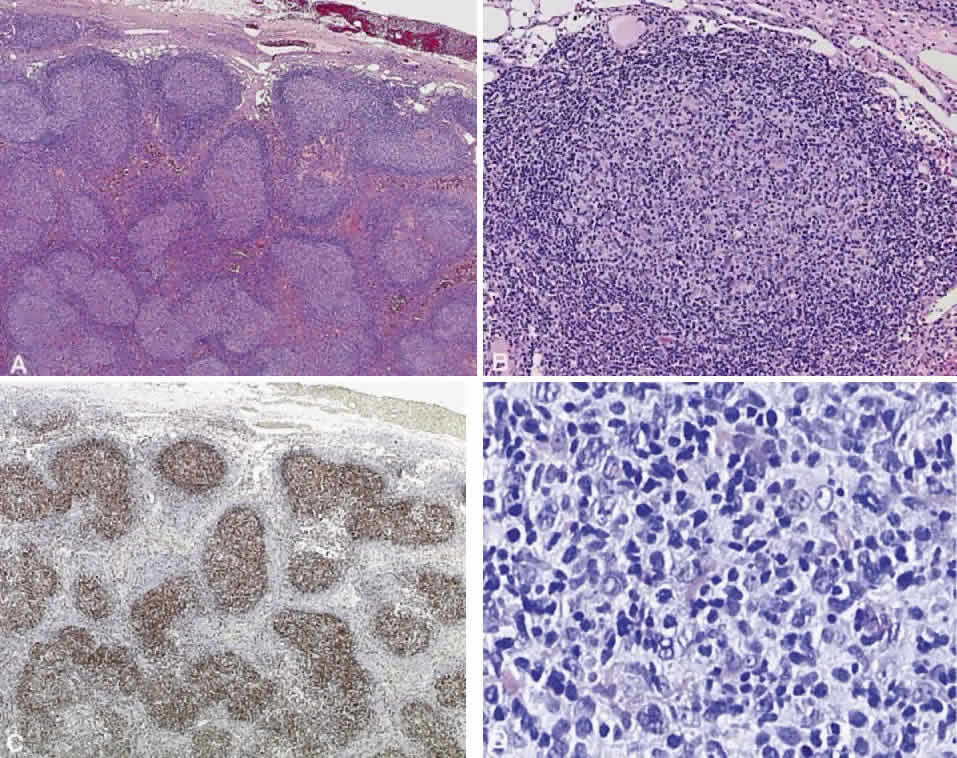

Numerous attempts have been made to classify lymphoid processes for clinical management and prediction of prognosis. Early classifications included only disease localized to the lymph node, which made classification of extranodal disease difficult and inaccurate. The Rappaport classification, first developed in 1956 and then modified in 1978, attempted to categorize lymphomas in two ways, first, using cytologic characteristics identified by conventional stains, and second, distinguishing between the follicular and diffuse growth pattern histologically38,39 (Table 3). The distinction of nodular, or follicular, and diffuse growth was considered useful because of the generally indolent nature of follicular growth, in which the tumor cell aggregates resemble germinal centers and disrupt the normal architecture of the node, compared with the appearance of diffuse growth, in which the lymph node is completely obliterated by a dense monotonous sheet of lymphocytes. In subsequent years, however, it was found that the descriptive growth pattern and cytogenetic characteristics of the Rappaport system did not predict prognosis reliably and were biologically inaccurate. The complexity of correlating degrees of differentiation, mitotic activity, and cytologic characteristics to prognosis have made lymphomas difficult to classify and have led to subsequent systems. The second system, proposed by Lukes-Collins in 1974, classifies lymphoma histologically according to its normal counterpart B-cell, T-cell, or null cell origin40,41 (see Table 3). Histologically, cells may appear small cleaved, large cleaved, small noncleaved, or large noncleaved, depending on the stage of B-cell arrest during normal transformation to immunoblast. Ninety percent of lymphomas are of B-cell origin, and the null cell also usually is of B-cell origin, although 10% may originate from T cells or histiocytes.42,43 Burkitt's lymphoma, the only lymphoma common in children, is a B-cell variant with a background of reactive histiocytes. As a result of histologic classification by Lukes-Collins, 76% of histiocytic lymphomas according to the Rappaport system were found to be not of histiocytic origin but of lymphocytic origin.40,44 The third system, the Working Formulation devised by the National Cancer Institute in 1982, attempted to predict prognosis by grouping lymphoma according to natural history, response to therapy, and overall survival.45 Three broad categories were established in terms of 5-year survival rates, the low-grade with a 50% to 70% survival rate, intermediate with 35% to 45%, and high grade with 23% to 32% (see Table 3). Orbital reactive hyperplasia, a relatively low-grade lesion, can be associated with systemic disease, whereas malignant or high-grade orbital lymphomas may be isolated findings. The Ann Arbor Staging Classification for Hodgkin's and non-Hodgkin's lymphomas was developed to stage disease based on systemic areas of involvement as a means of establishing a baseline for treating disease and following clinical progression46 (Table 4). Histologic classification, however, has been recognized as more useful than localization in the clinical management of nonHodgkin's lymphoma.47

While the Lukes-Collins and Working Formulation classifications were in wide use in the United States, the European literature made references to the Kiel and updated Kiel classifications, which led to disparities in classifying lymphoma. Another classification proposed by Jakobiec and coworkers was the most comprehensive classification available for orbital disease but failed to integrate systemic lymphoma, which is known to be associated in approximately half of cases.1 The most recent classification has made the system universal, comprehensive, and useful to interdisciplinary teams that characteristically manage patients with lymphoma. The International Lymphoma Study Group in 1994 developed the Revised European-American Lymphoma (REAL) classification (Table 5), which classifies lymphoid disease by the cell of origin into B-cell, T-cell, and natural killer cell lymphomas, leukemias, myeloma, and variants of Hodgkin's disease26 (Fig. 4). The identification of the putative benign progenitor cells has been inferred through the use of cell marker studies. The results of molecular genetic studies to identify immunoglobulin gene rearrangements and cytogenetic studies to detect chromosomal translocations in monoclonal proliferations have also been incorporated. A significant contribution of the REAL classification has been to incorporate primary extranodal lymphomas as recognizable and classifiable entities. As a result, new variants in this list include lymphoplasmacytic lymphoma, mantle cell lymphoma, marginal zone B-cell lymphoma, particularly mucosal-associated lymphoid tissue (MALT) lymphoma, subclasses of large cell lymphoma, and the natural killer cell lymphomas. Comparisons of the REAL classification to the Working Formulation and the Kiel classification are shown in Tables 6 and 7, respectively.48 The first series of 112 orbital lymphomas using the REAL classification reported the accuracy and utility of the system in classifying orbital lesions and predicting prognosis in combination with currently available immunophenotyping and immunocytogenetic studies.49 The REAL classification does not classify disease based on the degree of differentiation or clinical prognosis. However, a proposed prognostic scheme has been developed in accordance with the REAL classification28 (Table 8). In this text, tumor nomenclature adheres as strictly as possible to the REAL classification.